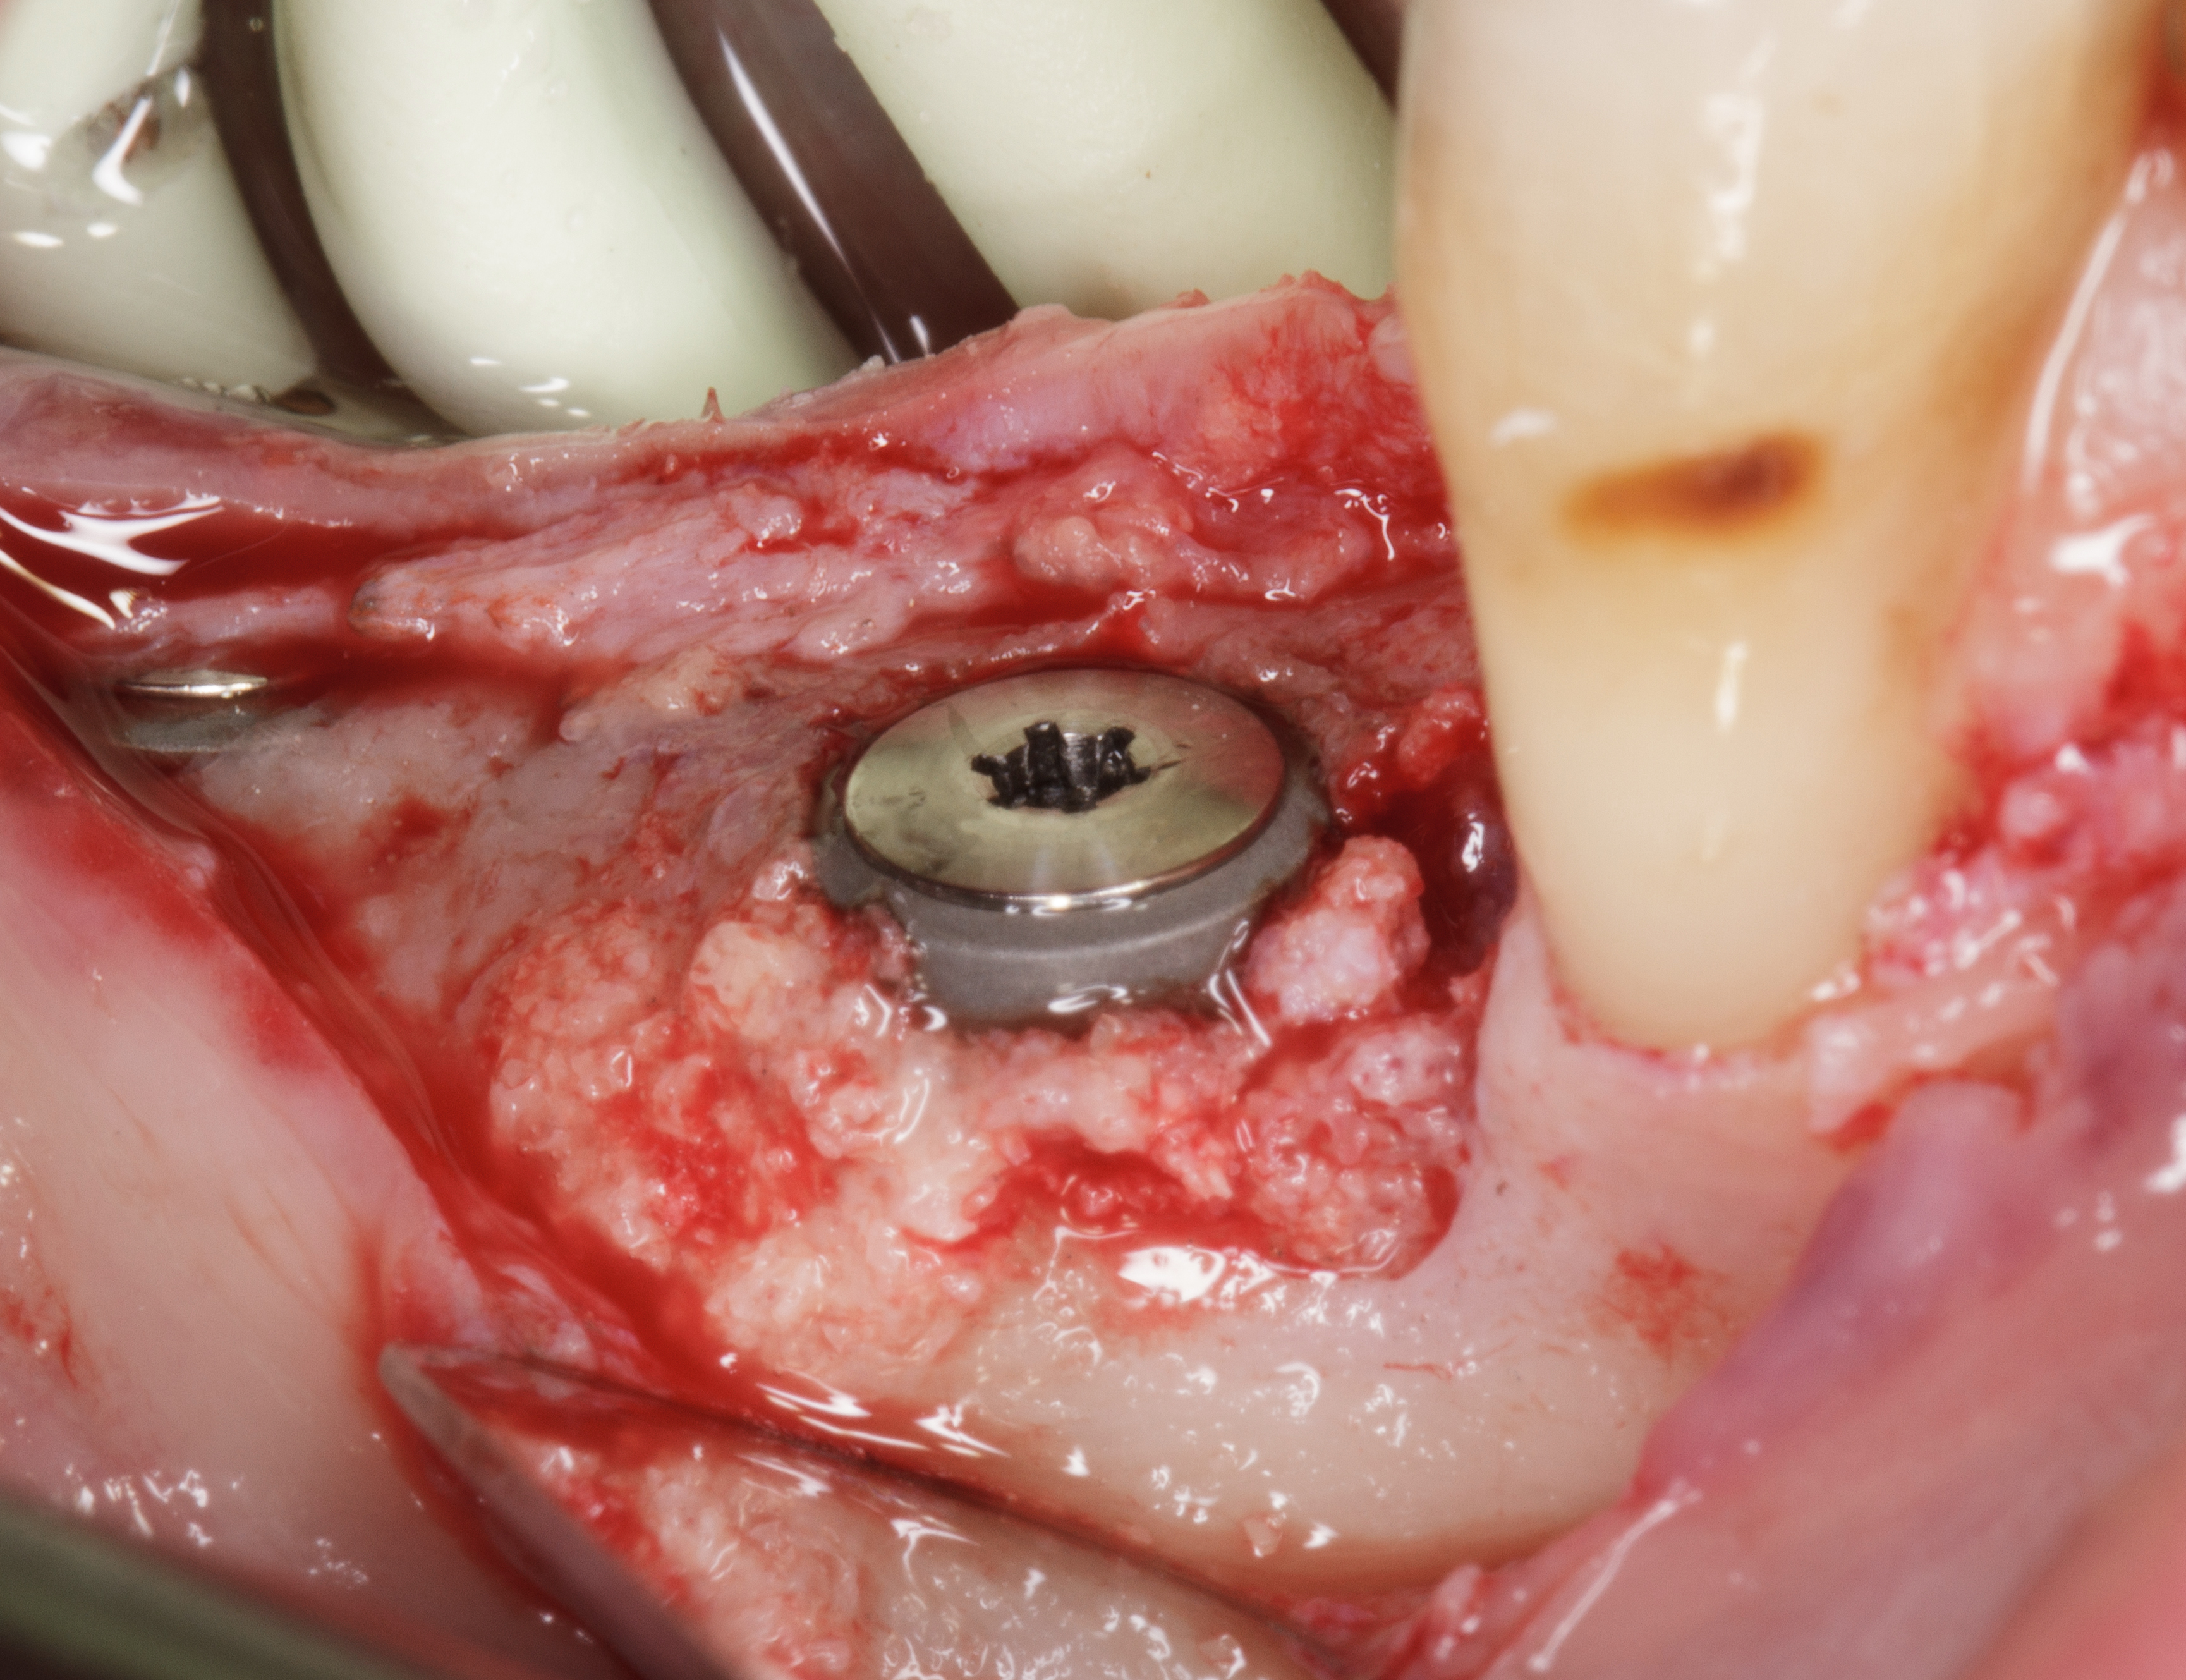

Questa situazione, anche se non prevista dal piano di trattamento iniziale, consente di valutare clinicamente a cielo aperto il pattern di guarigione ossea e connettivale nel primo mese dopo l’intervento rigenerativo post-estrattivo (Figura 12).

Dopo aver inciso un lembo mucoperiosteo senza incisioni di scarico verticali, si vede la zona oggetto di estrazione omogeneamente riempita da tessuto osteoide in fase di maturazione.

Una gran parte della membrana riassorbibile posta all’interno dell’alveolo è ancora ben evidente e adesa al tessuto in fase di maturazione.